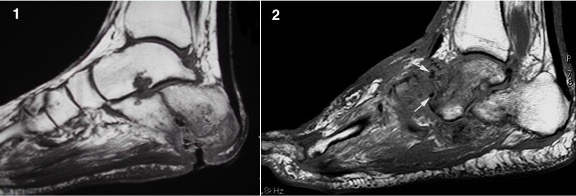

Fig 1: Osteomyelitis at calcaneal pressure point with marrow epicentre, cortical destruction and adjacent soft tissue ulcer.

Fig 2: Charcot midfoot with articular (TMTJ) epicentre, sclerotic bone fragments (arrows) and no soft tissue ulcer